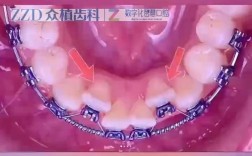

放置颊管

放置颊管是关键步骤,需确保位置准确:

- 用镊子夹取颊管(避免污染粘接剂面),对准磨牙颊侧中央:

- 垂直位置:颊管近中边缘位于牙冠中1/3,远中边缘平齐牙冠边缘;

- 近远中位置:颊管中心与牙冠中心一致,避免偏向近中或远中;

- 咬合方向:颊管牵引钩(若有)应朝向口腔前庭方向,避免干扰咬合;

- 轻压颊管,使其与牙面贴合,同时用探针去除多余粘接剂(避免溢出到牙龈或邻牙,刺激牙龈或导致邻牙龋坏)。